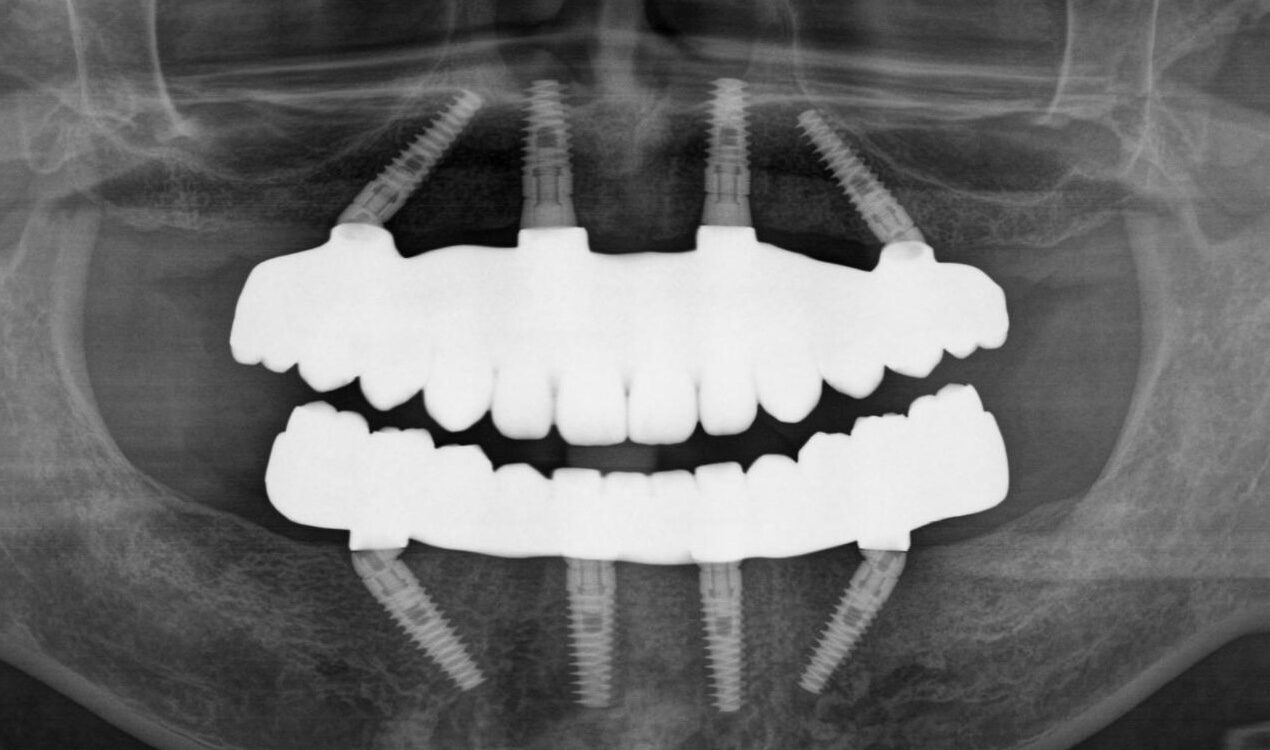

福岡県 46歳(女性)

「根本的な改善をしたい

内容 :上下顎オールオン4ザイゴマ0

費用 :4,822,400円

※モニター価格

期間 :半年

リスク:出血・腫れ・痺れ・痛み

他院で治療を行なっていましたが、根本的な改善には至らないまま不安な状態が続いていました。

カウンセリングで治療の流れや方法について詳しく説明を聞いて手術することを決意しました。

手術前は恐さがあり、緊張していましたが、想像していたような痛みはなく、うたた寝しているような感じでした。気づけば終わっていて、とても満足しています。

元々の自分の歯と比べると仮歯が入った段階でも綺麗になっていて嬉しかったです。この治療法を選んで良かったと思います。